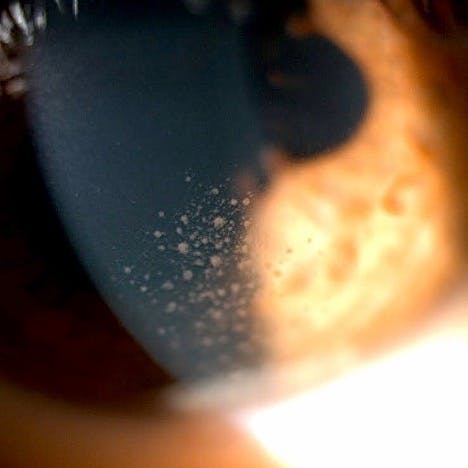

IMAGE OF THE WEEK

Arlt triangle of keratic precipitates.

Paul Hammond, OD, FAAO, @kmkoptometrypro